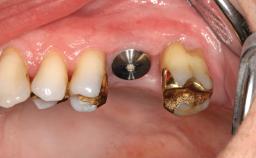

Implant Placement with Simultaneous SFE: Lateral Window Technique with a Composite Graft

A 68-year-old woman presented for treatment to replace her maxillary right second premolar and first molar. Three years previously, her general dental practitioner had extracted tooth 16 because of a perforated root canal with a developing interradicular lesion. The patient was satisfied with the chewing function of her premolar occlusion until tooth 15 became symptomatic 2 months before presentation. Since a root fracture had developed, this tooth had to be extracted as well. The patient was a non-smoker. She had continuously received dental care by her private practitioner. Her plaque control and gingival health was, for the most part, excellent. Periodontal probing depths never exceeded 3 mm. She displayed a medium smile line; her esthetic demands were moderate to high. Her gingival biotype was classified as medium, and the dentition revealed signs of bruxism.